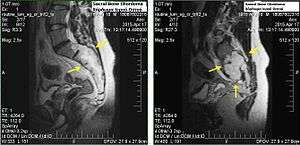

Chordomas can arise from bone in the skull base and anywhere along the spine. The two most common locations are cranially at the clivus and in the sacrum at the bottom of the spine.[1]

In most cases, complete surgical resection followed by radiation therapy offers the best chance of long-term control.[16] Incomplete resection of the primary tumor makes controlling the disease more difficult and increases the odds of recurrence. The decision whether complete or incomplete surgery should be performed primarily depends on the anatomical location of the tumor and its proximity to vital parts of the central nervous system.